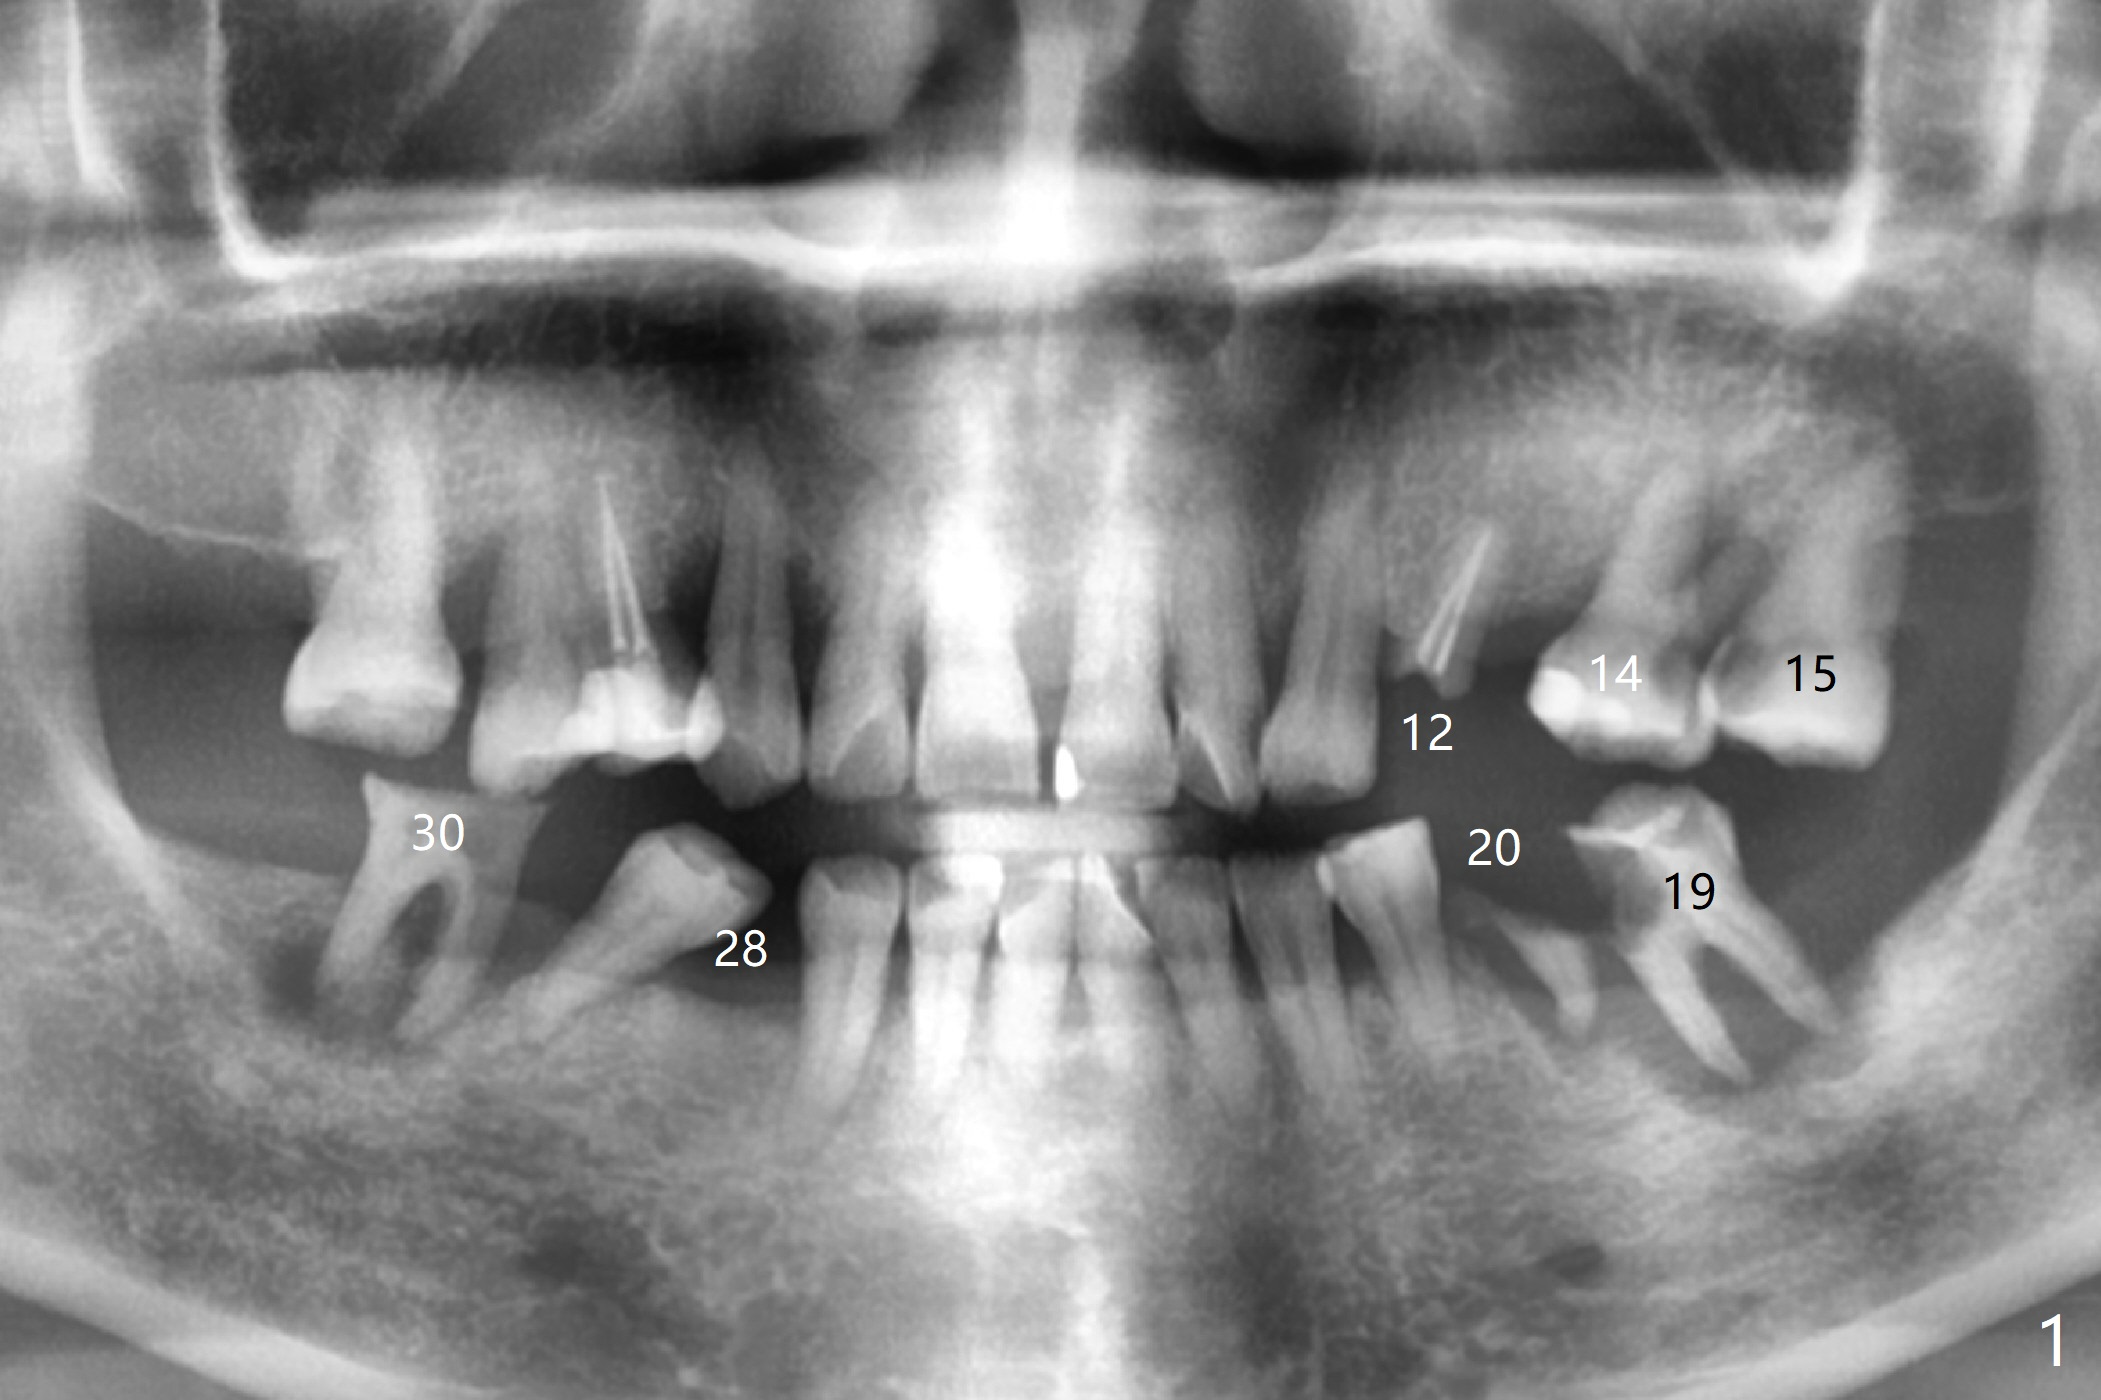

A 55-year-old woman has poor dentition, which is partially related to her previous history of ice chewing (Fig.1). The long bone height in the jaws suggests bruxism and requires as many teeth and implants as possible. After SRP, caries will be removed from #14 and 15 for determination of salvageability (Fig.2). The patient prefers to save the tooth #30. Endo referral will be recommended for #14 and 30. If the tooth #14 proves to be nonsalavageable, it will be extracted with #12 for immediate implants and subsequent FPD (Fig.3,4). Immediate implant will be avoided at #19 due to severe bone loss. Instead a short implant (5.5x5 or 6 mm) will be placed at #18, while a 4x11.5 mm one at #20 for FPD (Fig.5,6). All of the implant will use guides. There is a special point at #18. After use of 4.5 mm drill, the guide will be removed for free hand osteotomy using 5.0 mm drill, 5.5 mm tap and implant placement. PRF will be prepared for membrane and sticky bone at #19 and 20. For the lower right quadrant, treatment for #30 should be conducted first, either RCT or implant. The tooth #29 will be uprighted using #30 as an anchor, if the former is salvageable. The implant at #28 will be placed last (Fig.7,8).